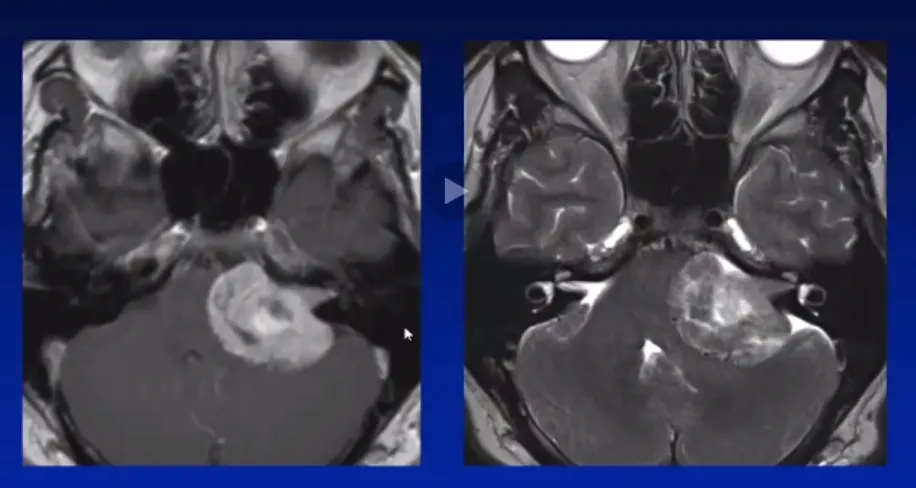

36岁的卢卡,怎么也想不到持续的耳鸣和逐渐下降的听力背后,藏着一个潜伏的肿瘤超过3cm的巨大听神经瘤。 幸运的是,卢卡最终在国际知名神经外科教授的操刀下顺利完成手术,肿瘤被完整切...